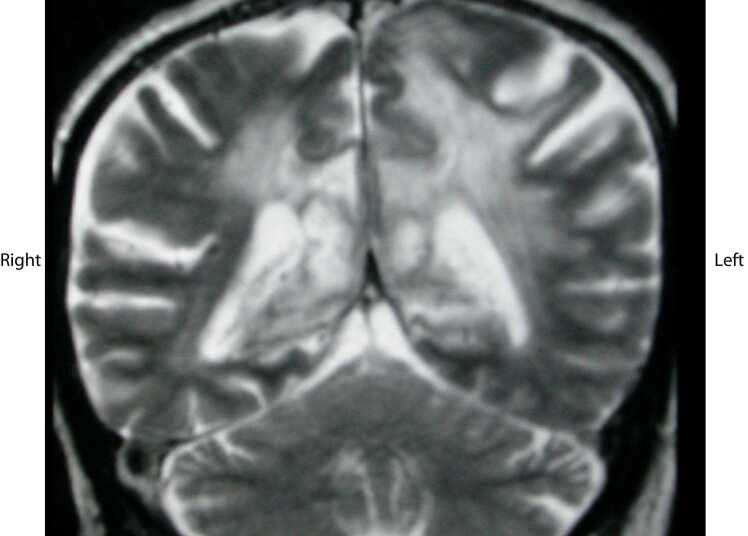

The authors report a case of varicella zoster encephalitis, mimicking a glioblastoma on Magnetic Resonance Imaging (MRI) and Magnetic Resonance Spectroscopy (MRS). The limitations of MRI/MRS, may lead to delayed treatment with antiviral agents, which can result in increased morbidity and mortality. The possibility of viral encephalitis should remain in the differential diagnosis of all patients presenting with headaches and confusion, even when imaging results are indicative of a neoplastic process.

Abstract Image